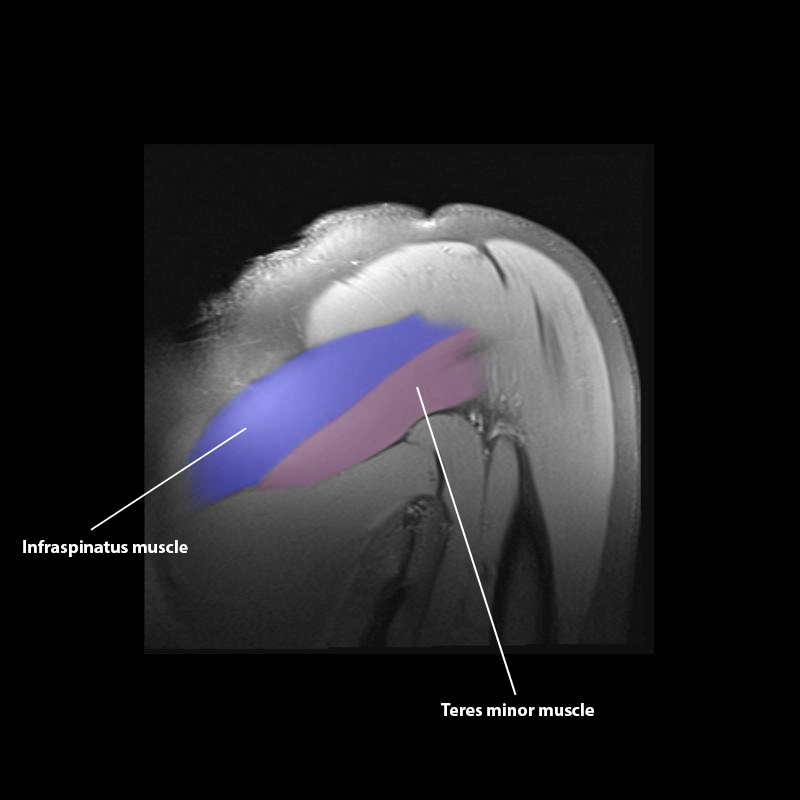

Shoulder MRI Anatomy